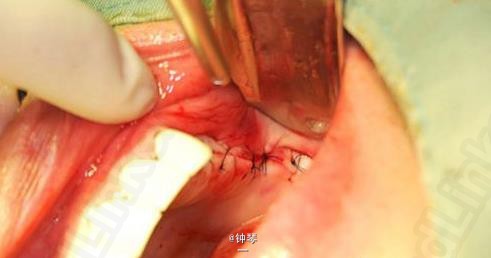

刀刃状牙槽嵴种植+钛网应用

左上3、4、6种植

种植体良好。